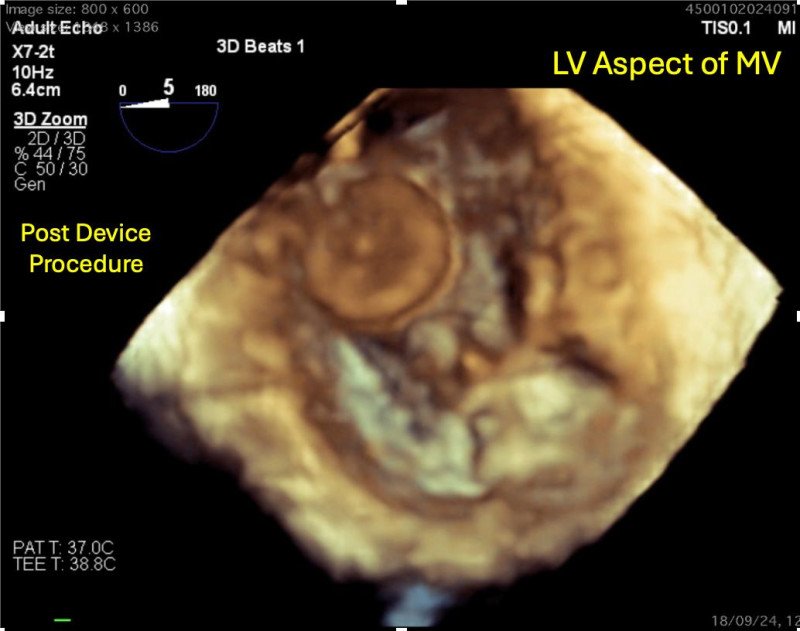

भोपाल। एम्स में हाल ही में दुर्लभ समस्या माइट्रल वाल्व परफोरेशन (दिल के वाल्व की दीवार में छेद) का सफल इलाज किया गया है। जिसके लिए बेहद जटिल प्रक्रिया ट्रांसकैथेटर विधि अपनाई गई। यह अपनी तरह का देश का दूसरा मामला है। एम्स से मिली जानकारी के अनुसार 18 वर्षीय मरीज के वाल्व की दीवार से रक्त स्राव हो रहा था। उसे सांस लेने तक में तकलीफ हो रही थी। वे बेहतर इलाज की तलाश में एम्स आया, जहां मरीज का इलाज किया गया।डॉ. भूषण ने कहा कि मरीज की आयु बेहद कम थी।

ऐसे में वाल्व बदलते तो उसे आगे भविष्य में रोजाना खून पतला करने की गोलियां खानी पड़ती। मेटेलिक वाल्व लगने से इंफेक्शन का खतरा भी बना रहता है। यह वजह रही कि मरीज की बेहतर जिंदगी के लिए इस जटिल विधि का किया प्रयोग।एम्स के कार्डियोलॉजिस्ट डॉ. भूषण शाह ने बताया कि दिल के वाल्व की दीवार से रक्तस्राव बेहद कम देखने को मिलता है। आमतौर पर वाल्व के खुलने व बंद होने में समस्याएं सामने आती हैं।

जिनका कारण रूमेटिक हृदय रोग, संक्रमण संयोजी ऊतक विकार या वाल्व की जन्मजात असामान्यता होती है। जबकि मरीज में ऐसे कोई लक्षण नहीं पाए गए।स्थिति समझने के लिए 3डी ट्रांसइसोफेगल इकोकार्डियोग्राफी (टीईई) जांच की गई। यह जांच पेट के रास्ते एक ट्यूब डाल कर की जाती है। इसी तकनीक की मदद और 3डी तस्वीर से तैयार हुए मैप के जरिए ट्रांसकैथेटर (ट्यूब) को छेद तक पहुंचाया गया।